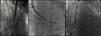

The procedure was performed in the catheterization laboratory, the team members being specially positioned for this approach (Figure 2). The proximal left common carotid artery was exposed under general anesthesia. Thereafter, sequential dilation of the carotid artery was performed and an 18F vascular access sheath was carefully advanced into the ascending aorta. The valve delivery system was then advanced and a 29 mm CoreValve Evolut R self-expanding prosthetic valve was successfully deployed. There was no residual gradient or significant aortic regurgitation (Figure 3, Video 1). The patient was discharged five days after the procedure without complications.